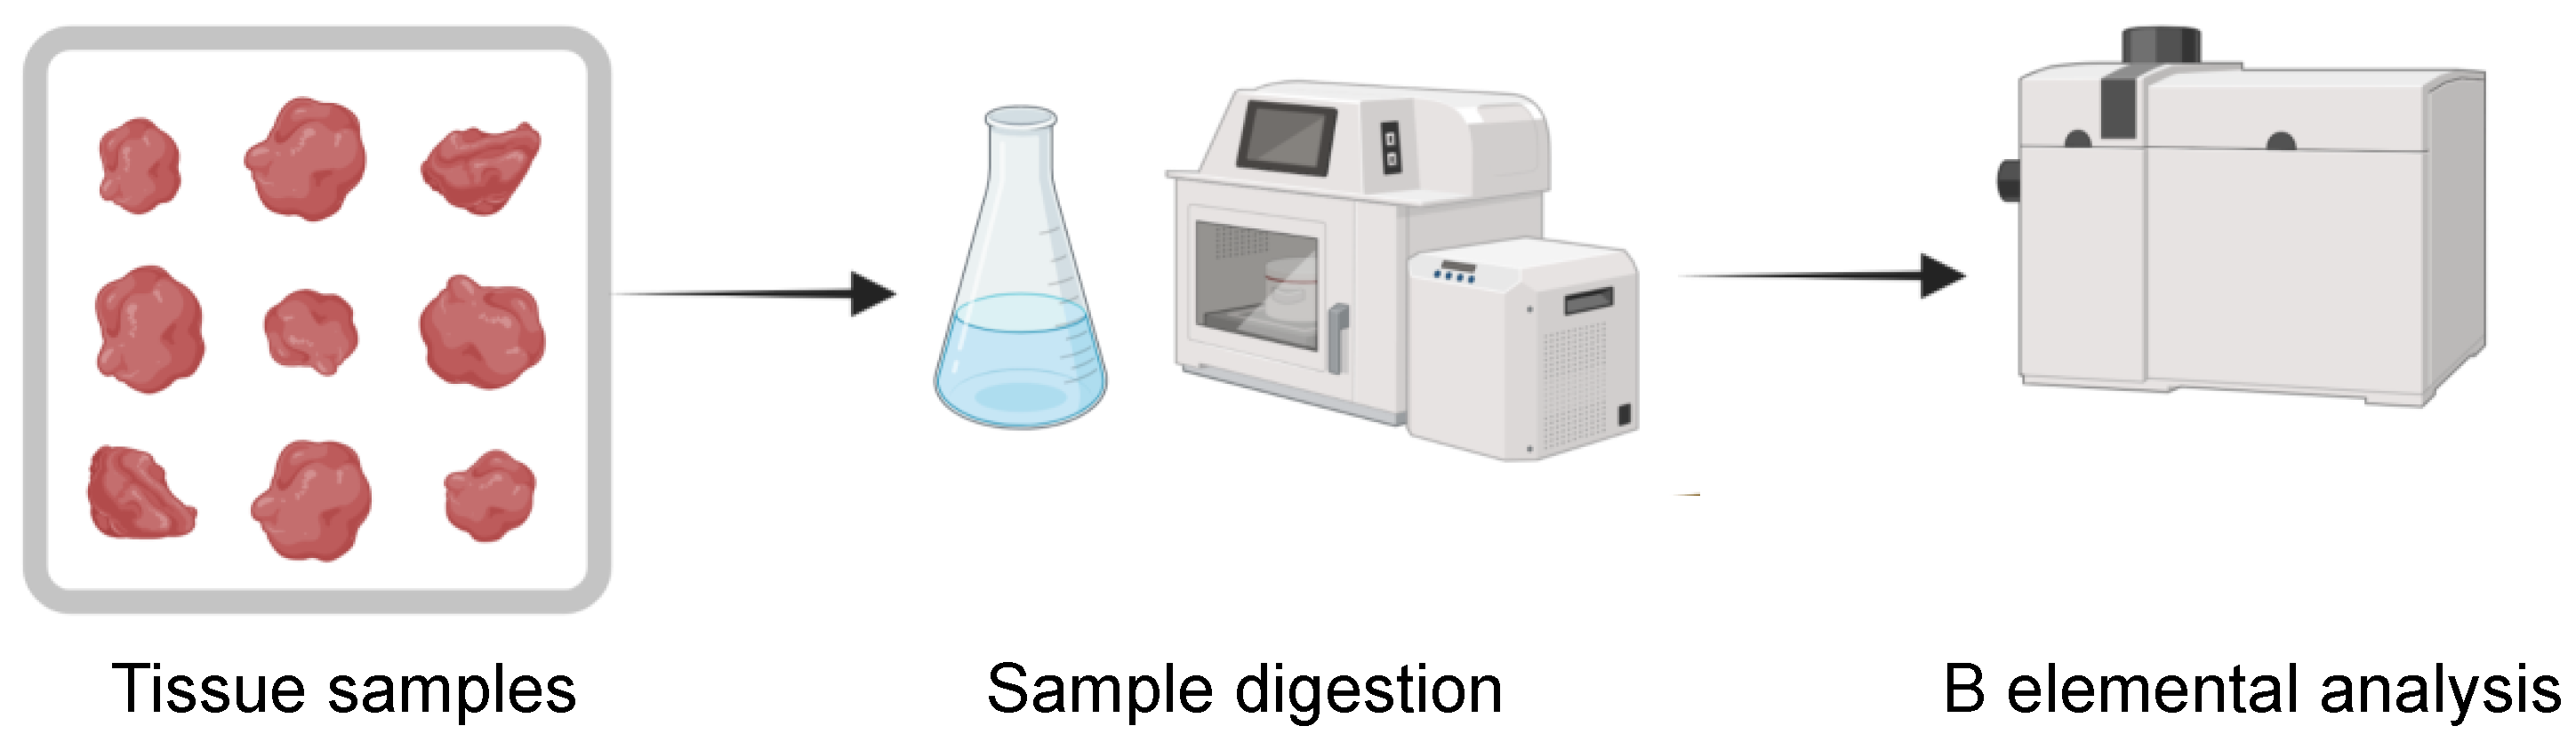

3.2. Boron Elemental Analysis Techniques